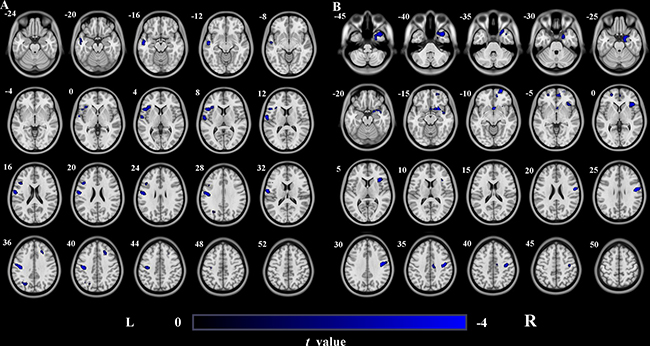

Using a strict statistical threshold (P < 0.05, FWE cluster-level correction combined with uncorrected P < 0.005), compared to the healthy controls, stroke patients with left lesions exhibited significantly decreased GMV in the left sensorimotor cortex (SMC) (Figure 2A), and patients with right lesions showed significantly decreased GMV in the right SMC (Figure 2B). Under a loose statistical threshold (P < 0.01, uncorrected), patients with left lesions additionally showed decreased GMV in the left insular cortex, middle temporal cortex, middle occipital cortex, triangular part of the inferior frontal gyrus (IFG), and right middle frontal gyrus (MFG) (Figure 3A); patients with right lesions also showed decreased GMV in the right insular cortex, middle temporal cortex, dorsal posterior cingulate cortex (PCC), orbitofrontal cortex, and left superior frontal cortex (Figure 3B).

Figure 3: GMV decrease in patients with left- and right-sided lesions compared to healthy controls (uncorrected P < 0.01, cluster size>100). (A) Stroke patients with left-sided lesions exhibit decreased GMV in L_Ins, L_MTG, L_SMC, R_MFG, L_MOG and triangular part of L_IFG compared to healthy controls. (B) Stroke patients with right-sided lesions exhibit decreased GMV in R_Ins, R_MTG, R_SMC, R_dPCC, R_OFC and L_SFG compared to healthy controls. Abbreviations: d, dorsal; GMV, grey matter volume; IFG, inferior frontal gyrus; Ins, Insula; L, left; MFG, middle frontal gyrus; MOG, middle occipital gyrus; MTG, middle temporal gyrus; OFC, orbitofrontal cortex; PCC, posterior cingulated cortex; R, right; SFG, superior frontal gyrus; SMC, sensorimotor cortex.